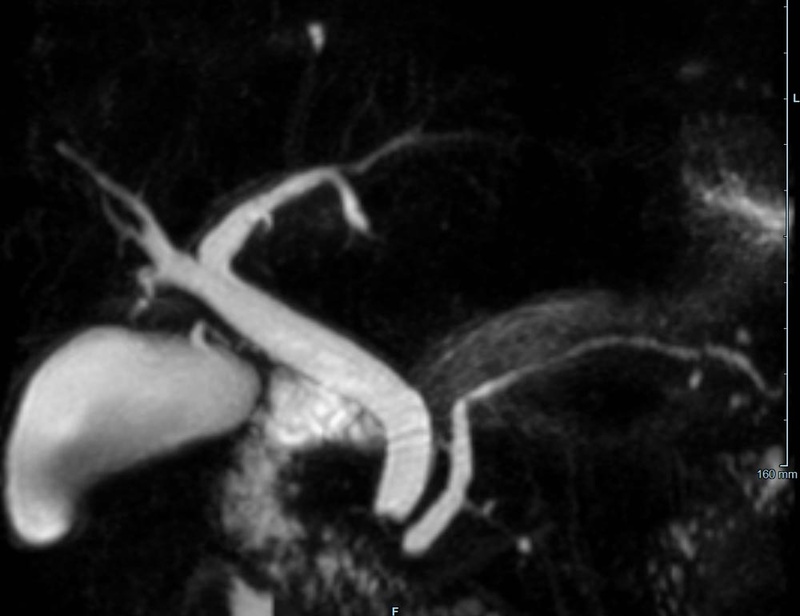

- Gallenwegssystem

- Nichtinvasive Darstellung der Gallenwege (MRCP)

- Abklärung der Ursache einer Gallenabflussbehinderung (Tumor, Gallensteine, Entzündung)

- Pankreas

- Diagnostik des Pankreaskarzinoms und Pankreasentzündung

- weitere Einordnung von Pankreaszysten (z.B. Pseudozysten, IPMN)

- Therapieverlaufskontrolle